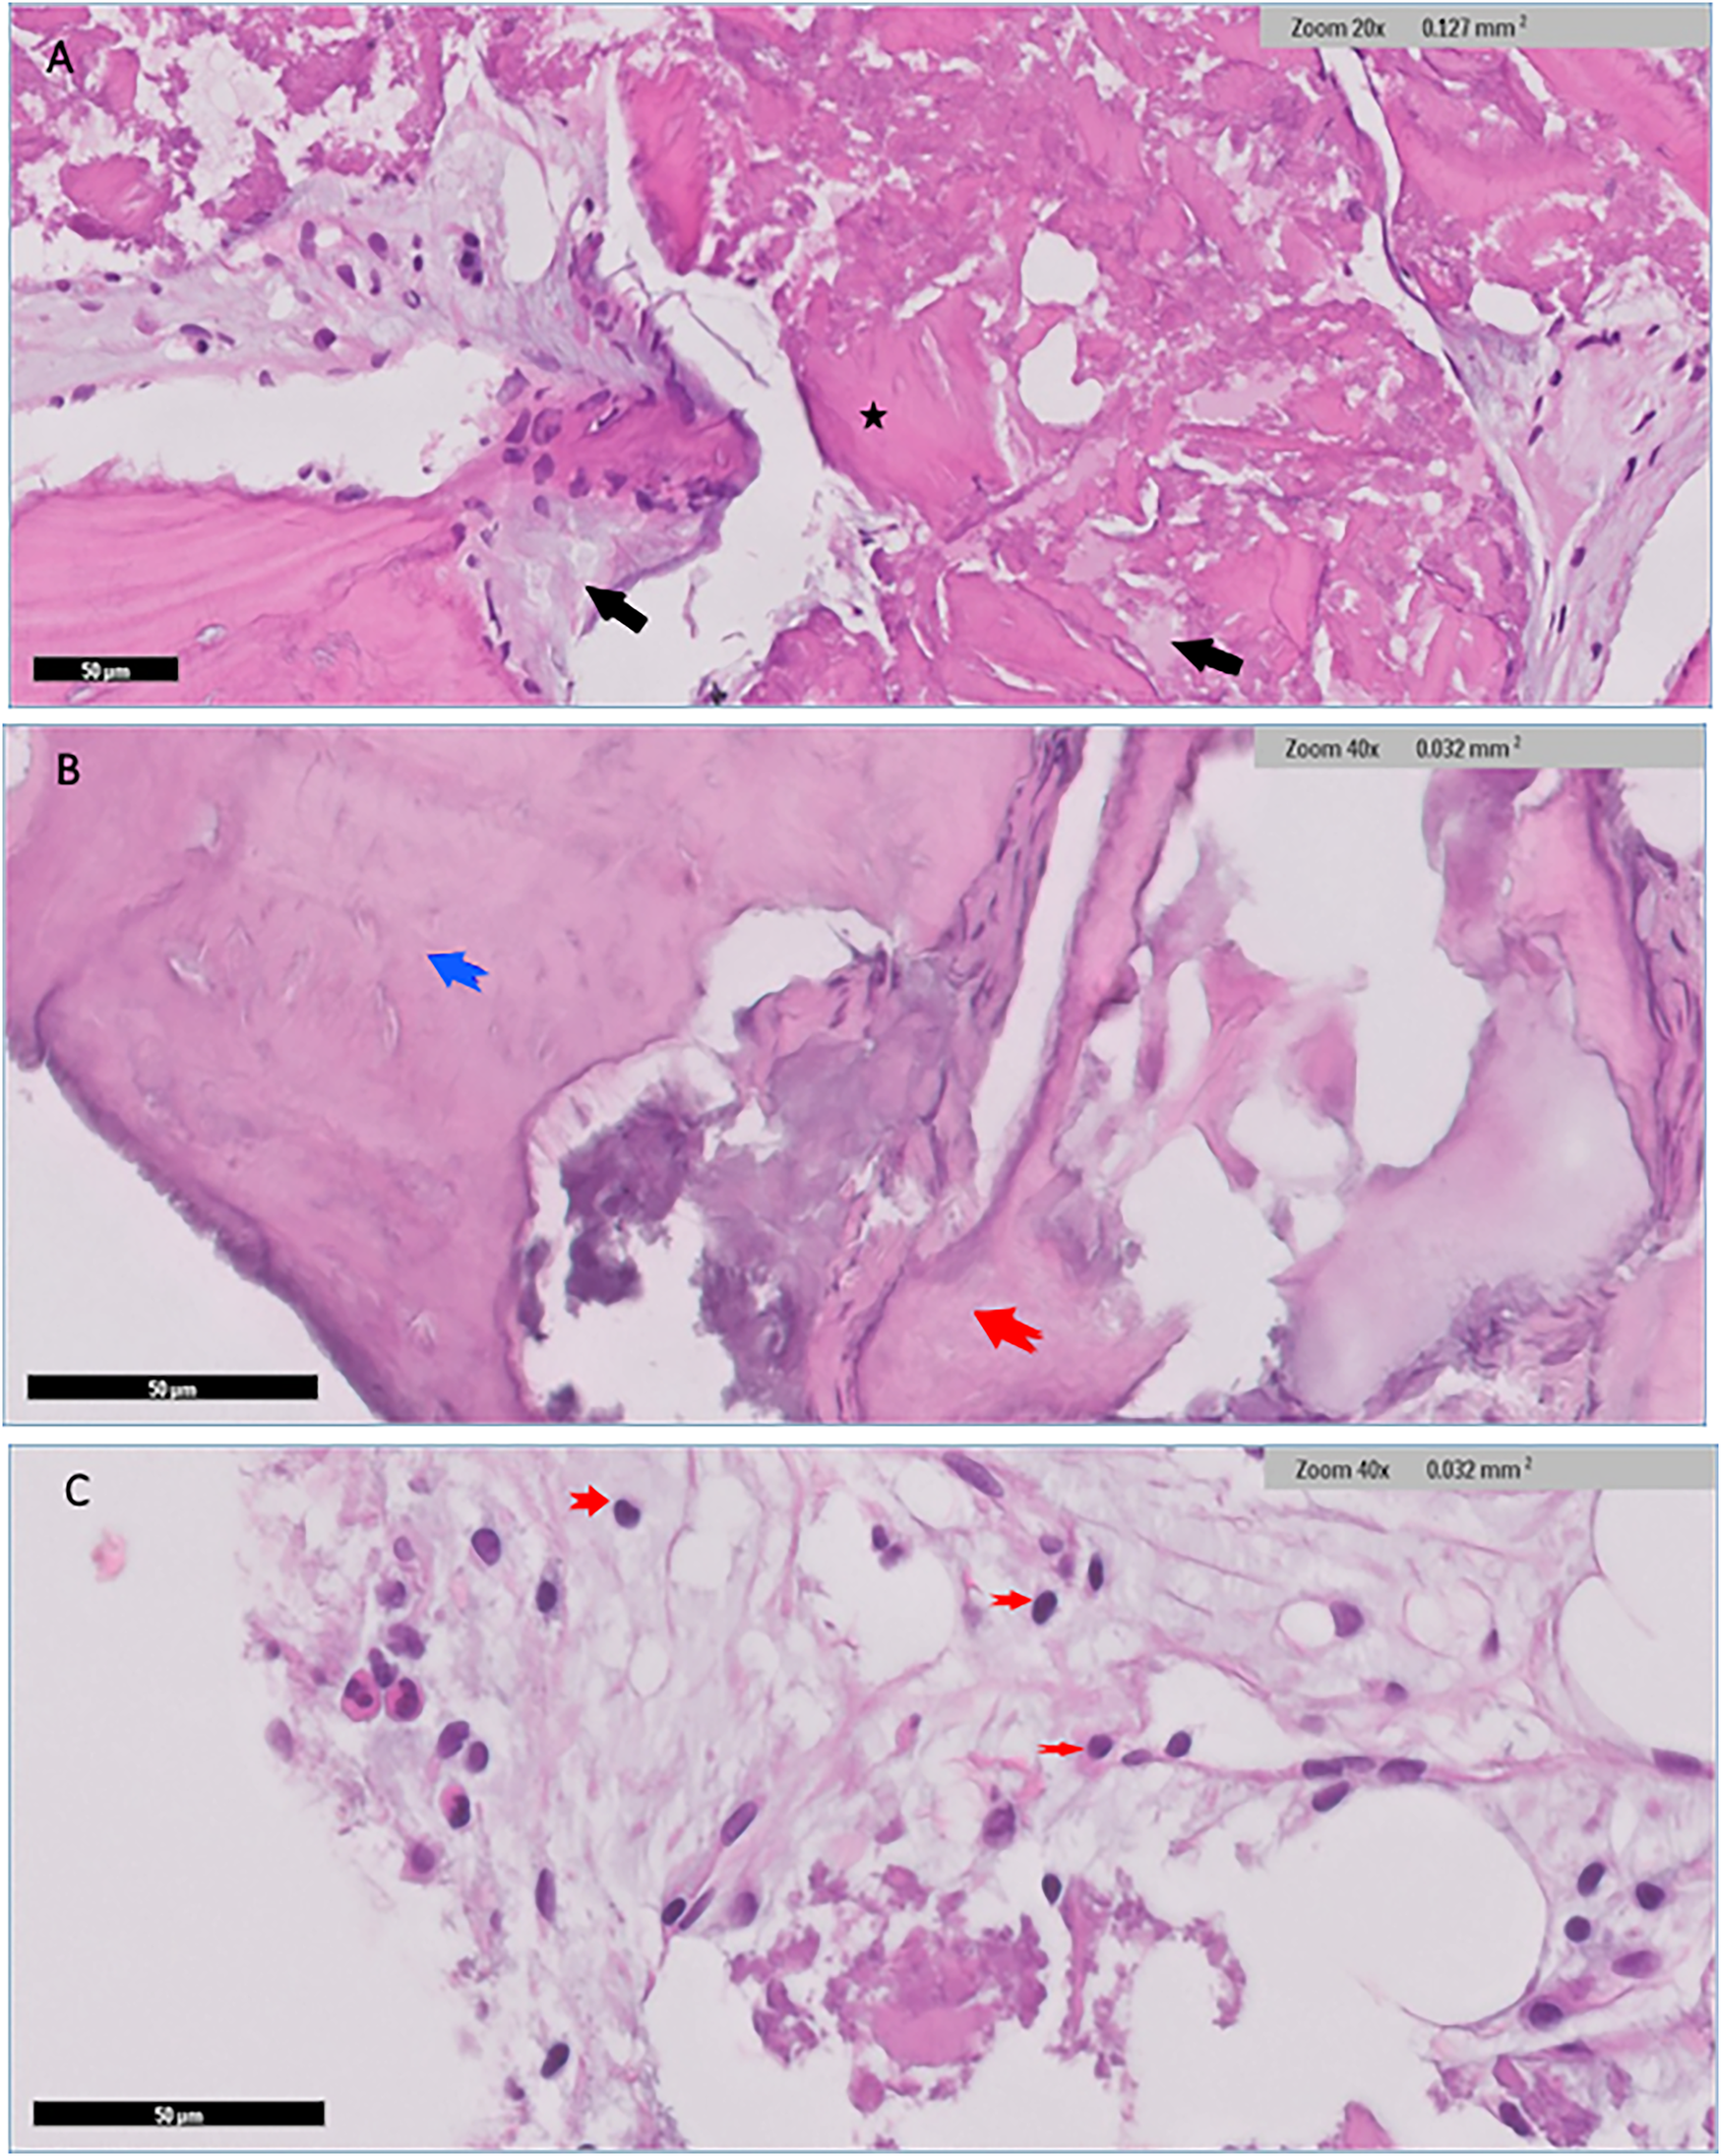

Figure 7

Histological findings for Bio-Oss group revealed admixture of native mature lamellar cortical bone with grafted bone (black arrows), and with evidence of minimal focal integration (A) Other areas demonstrated well preserved lamellar cortical/grafted bone integration with evidence of viable osteocytes *(A) Cellular immature/ woven bone was observed (blue arrow), features of grafted bone that were devoid of cells showing evidence of integration (red arrow) (B) Clusters of neutrophils (red arrows) were also seen in myxoid background (C).

Low power histological examination of the Bio-Oss group revealed admixture of native mature lamellar cortical bone and grafted bone. There was only focal minimal evidence of integration in some areas, while in others, preserved well-preserved lamellar cortical/grafted bone integration with evidence of viable osteocytes, resting lines and evidence of focal maturation was seen. Clusters of neutrophils were also present in myxoid background. Cellular immature/ woven bone was observed. Hypocellular fibrous tissue supporting fragments of grafted bone that are devoid of cells showing evidence of integration with mature lamellar cortical bone in several places within the section. scattered irregular fragments of grafted bone supporting well-preserved nuclei were also identified in places. The otherwise well-vascularized fibrocollagenous stroma also contains scattered macrophages. Few giant cells were seen at the edges of the section in places (Figure 7).

In the Bio-Oss group, we found minimal focal integration between native mature lamellar cortical bone and grafted bone, with evidence of viable osteocytes and resting lines. This observation aligns with Artzi et al. (29), who reported cellular presence in extraction sites filled with Bio-Oss. In agreement with previous studies (30, 31) Our findings of clusters of neutrophils and scattered macrophages, with few giant cells at section edges, parallel the inflammatory responses. However, the inflammatory response patterns vary in the literature. While Piatteli et al. (32), Molly et al. (33) and Degidi et al. (34) reported no significant inflammatory cell presence with Bio-Oss, our observations showed a moderate inflammatory response. This variation might be attributed to methodological differences and surgical techniques, as suggested by previous studies.